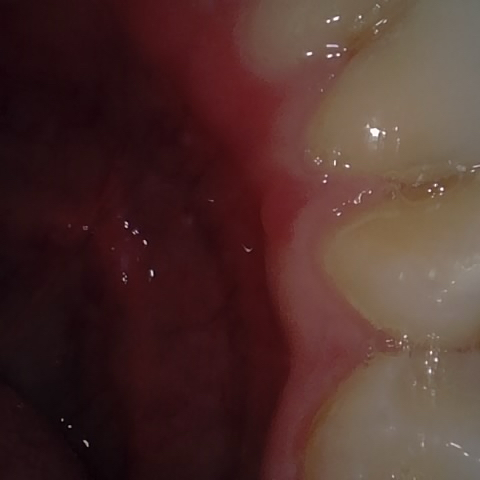

Annotated as "Good"